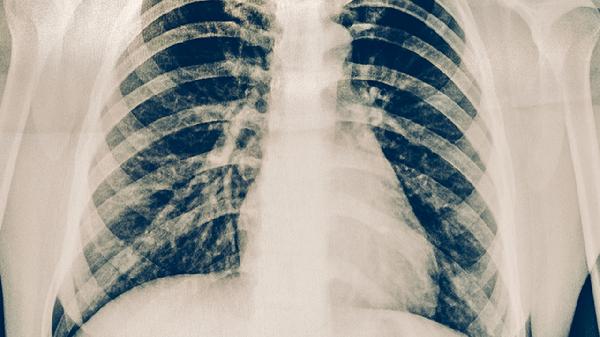

肺积水胸腔积液的严重程度取决于病因和积液量,轻度积液可能由肺炎等感染引起,大量积液可能提示心力衰竭、恶性肿瘤等严重疾病。

心力衰竭导致肺静脉压力升高时,会出现双侧胸腔积液,可能伴有呼吸困难、下肢水肿。需利尿剂治疗原发病,积液量大时需穿刺抽液。

肺癌胸膜转移或恶性胸膜间皮瘤可引起血性胸腔积液,常伴随消瘦、胸痛。需通过胸水细胞学检查确诊,治疗包括胸腔灌注化疗和全身治疗。